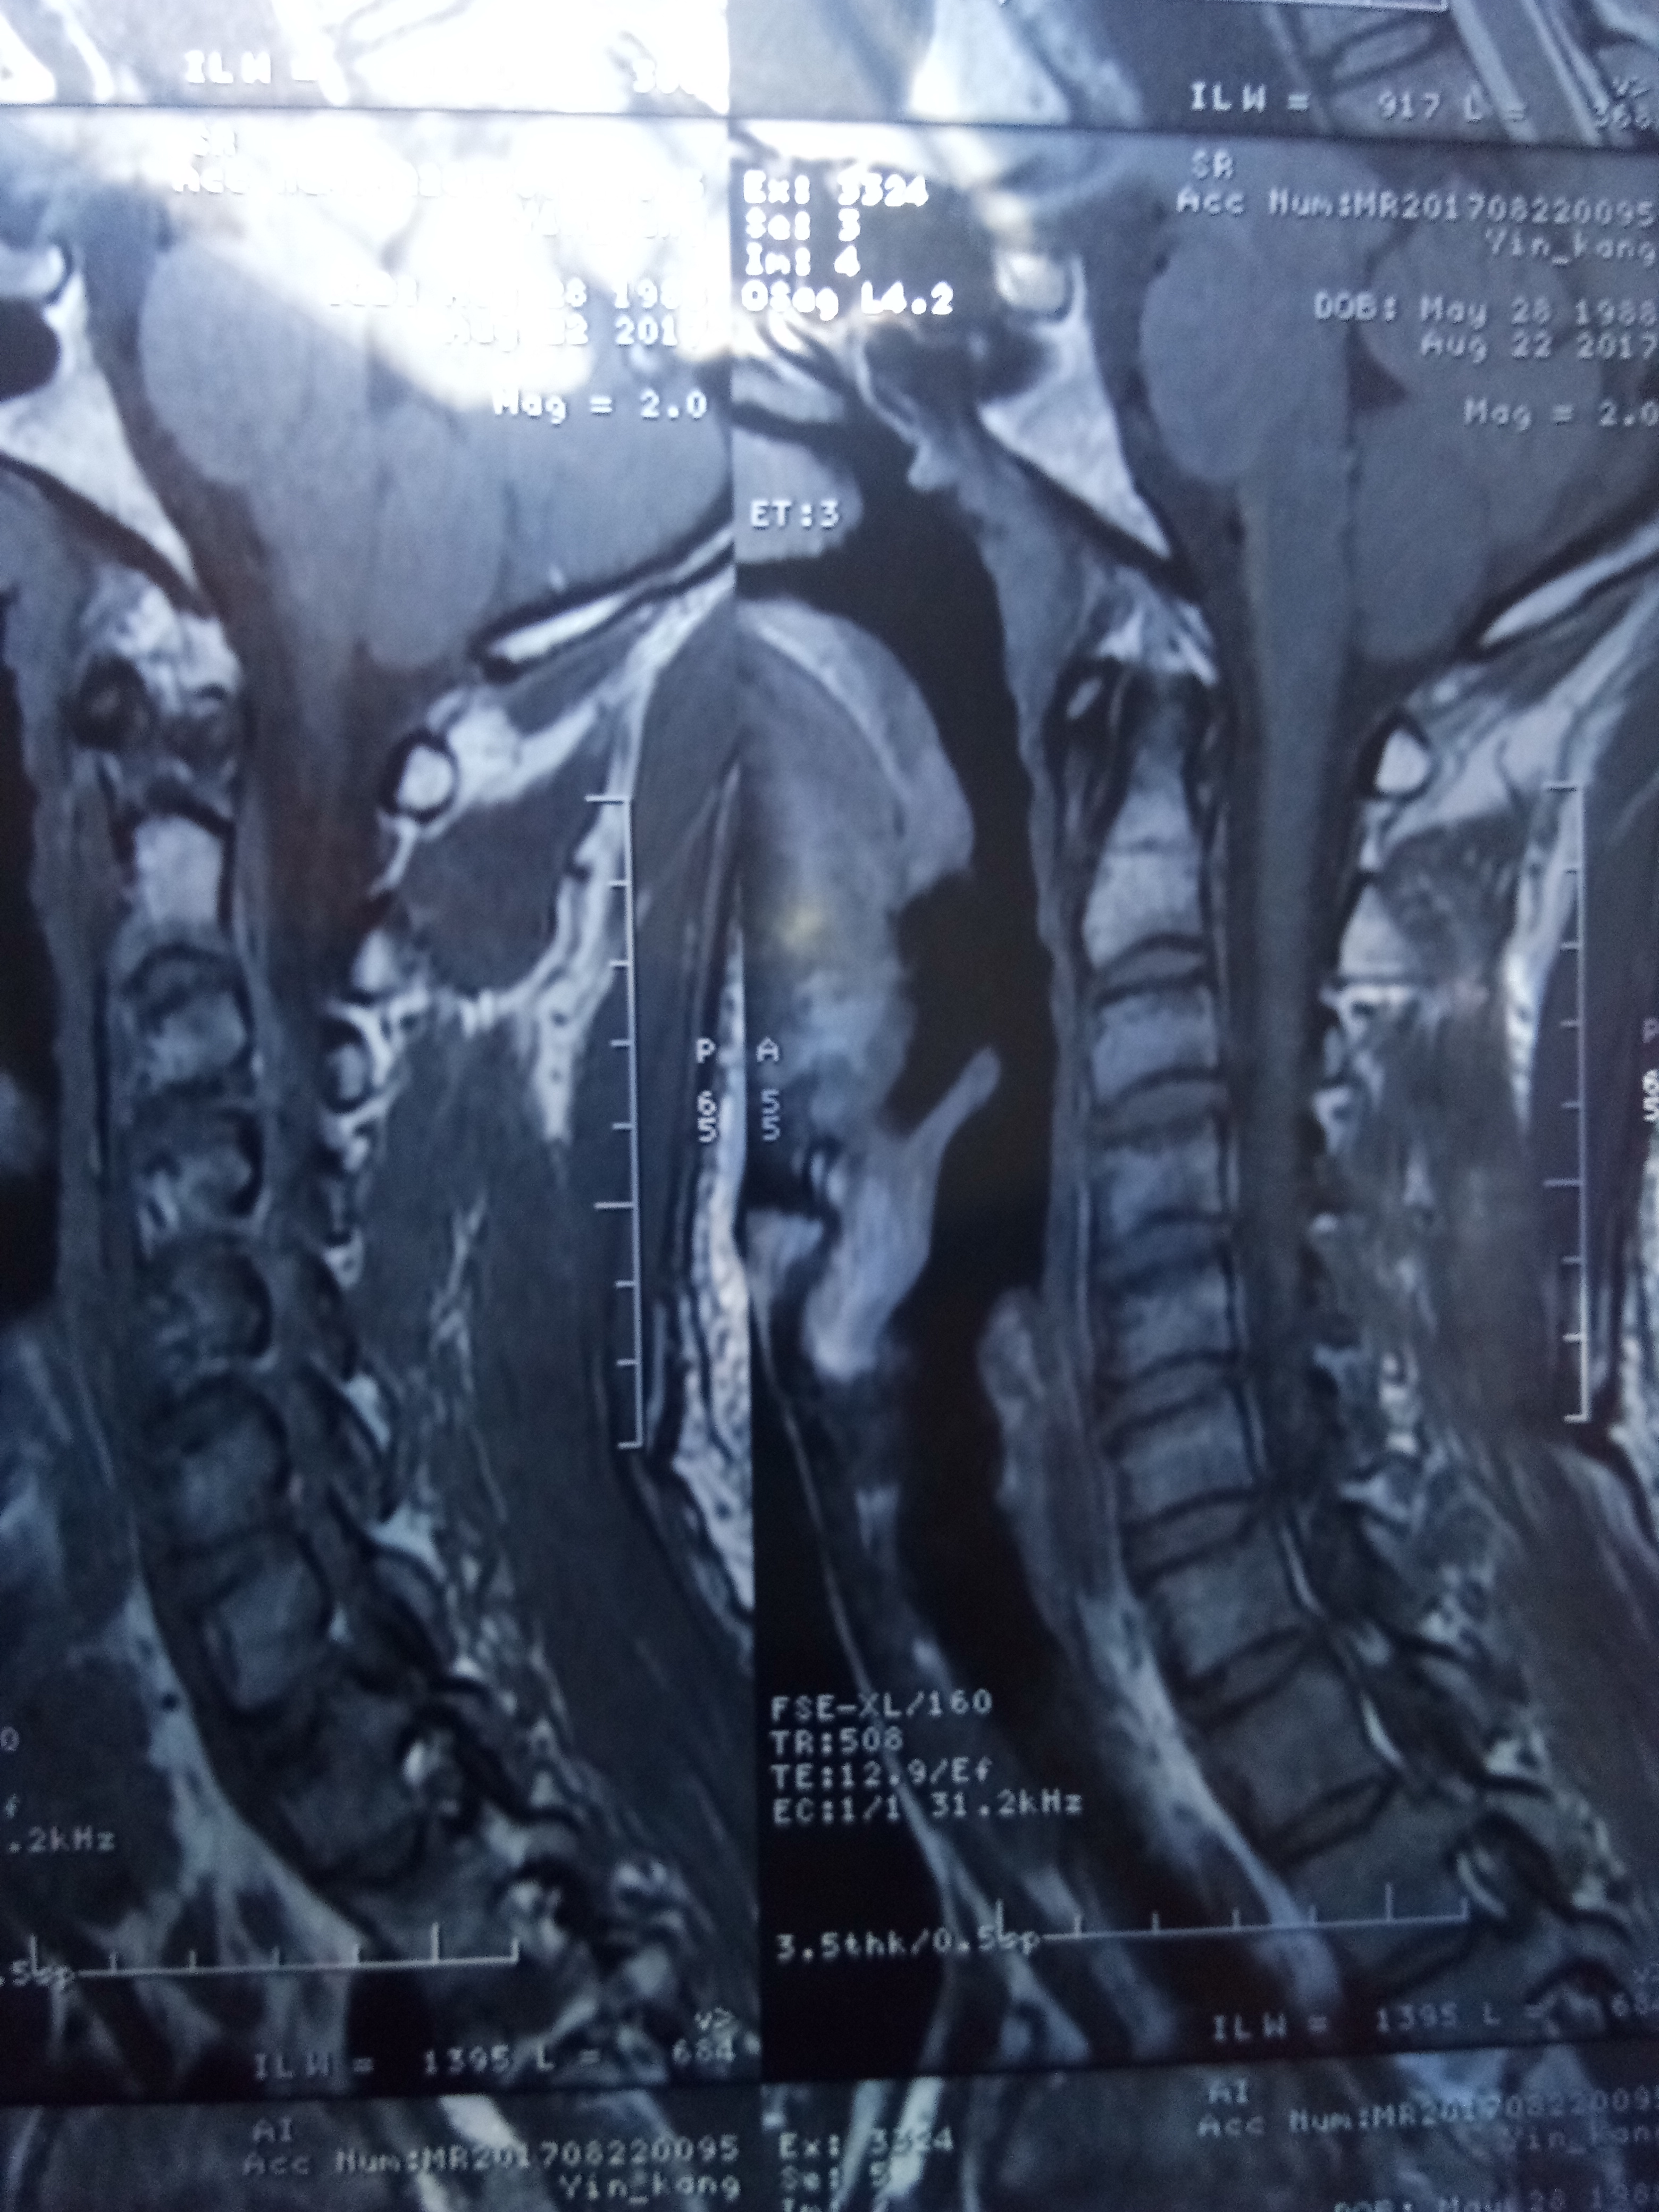

有颈椎病导致高血压的吗,25岁 血压 95 138

颈椎病会引起高血压,神经受压迫,适当的锻炼,注意饮食,这么年轻会没事的